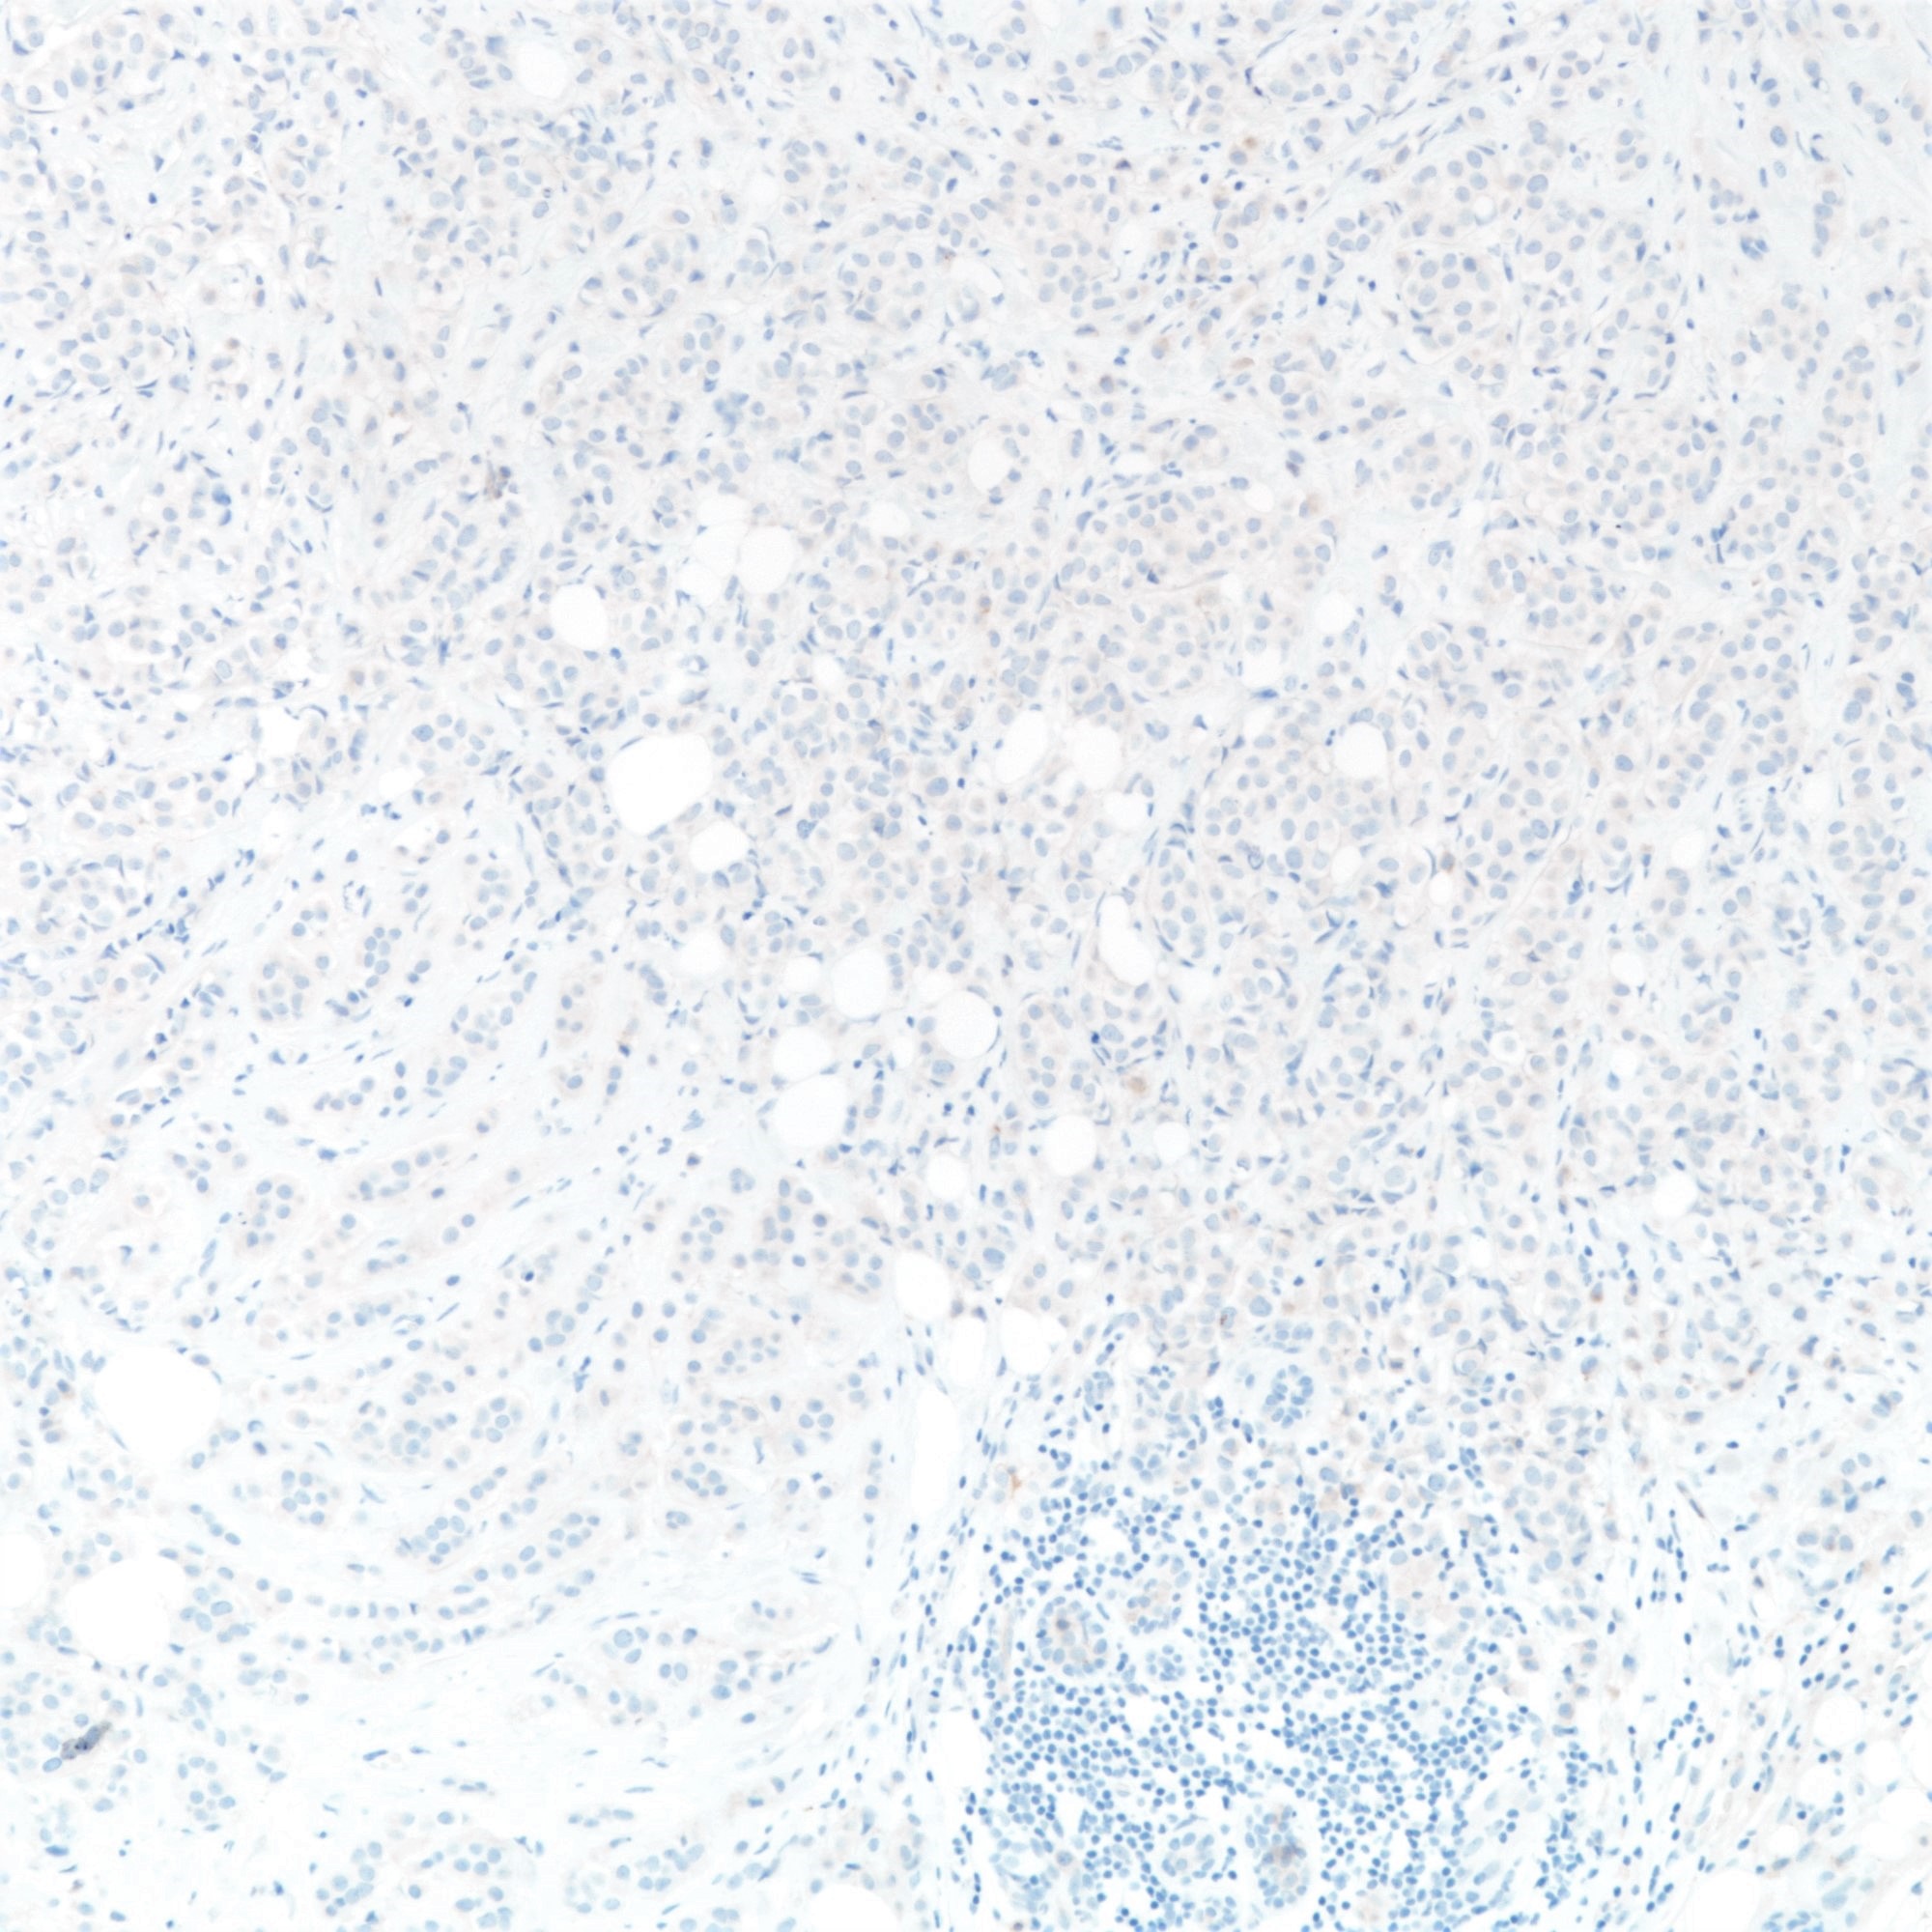

- Loss of E-cadherin expression on immunohistochemistry helpful but not required for diagnosis

- Majority of lobular carcinomas show loss of E-cadherin expression (Am J Surg Pathol 2010;34:1472)

- E-cadherin (16%) (Am J Surg Pathol 2010;34:1472, Hum Pathol 2020;102:44)

- E-cadherin absence or reduction of membranous staining, useful but not necessary for diagnosis of lobular carcinoma

- E-cadherin (16%) (Am J Surg Pathol 2010;34:1472, Hum Pathol 2020;102:44)